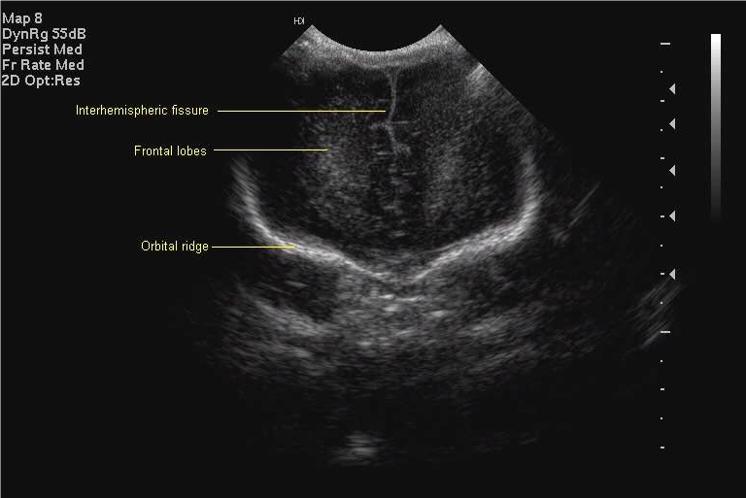

Standard views for cranial ultrasonography of the newborn

Anterior Coronal